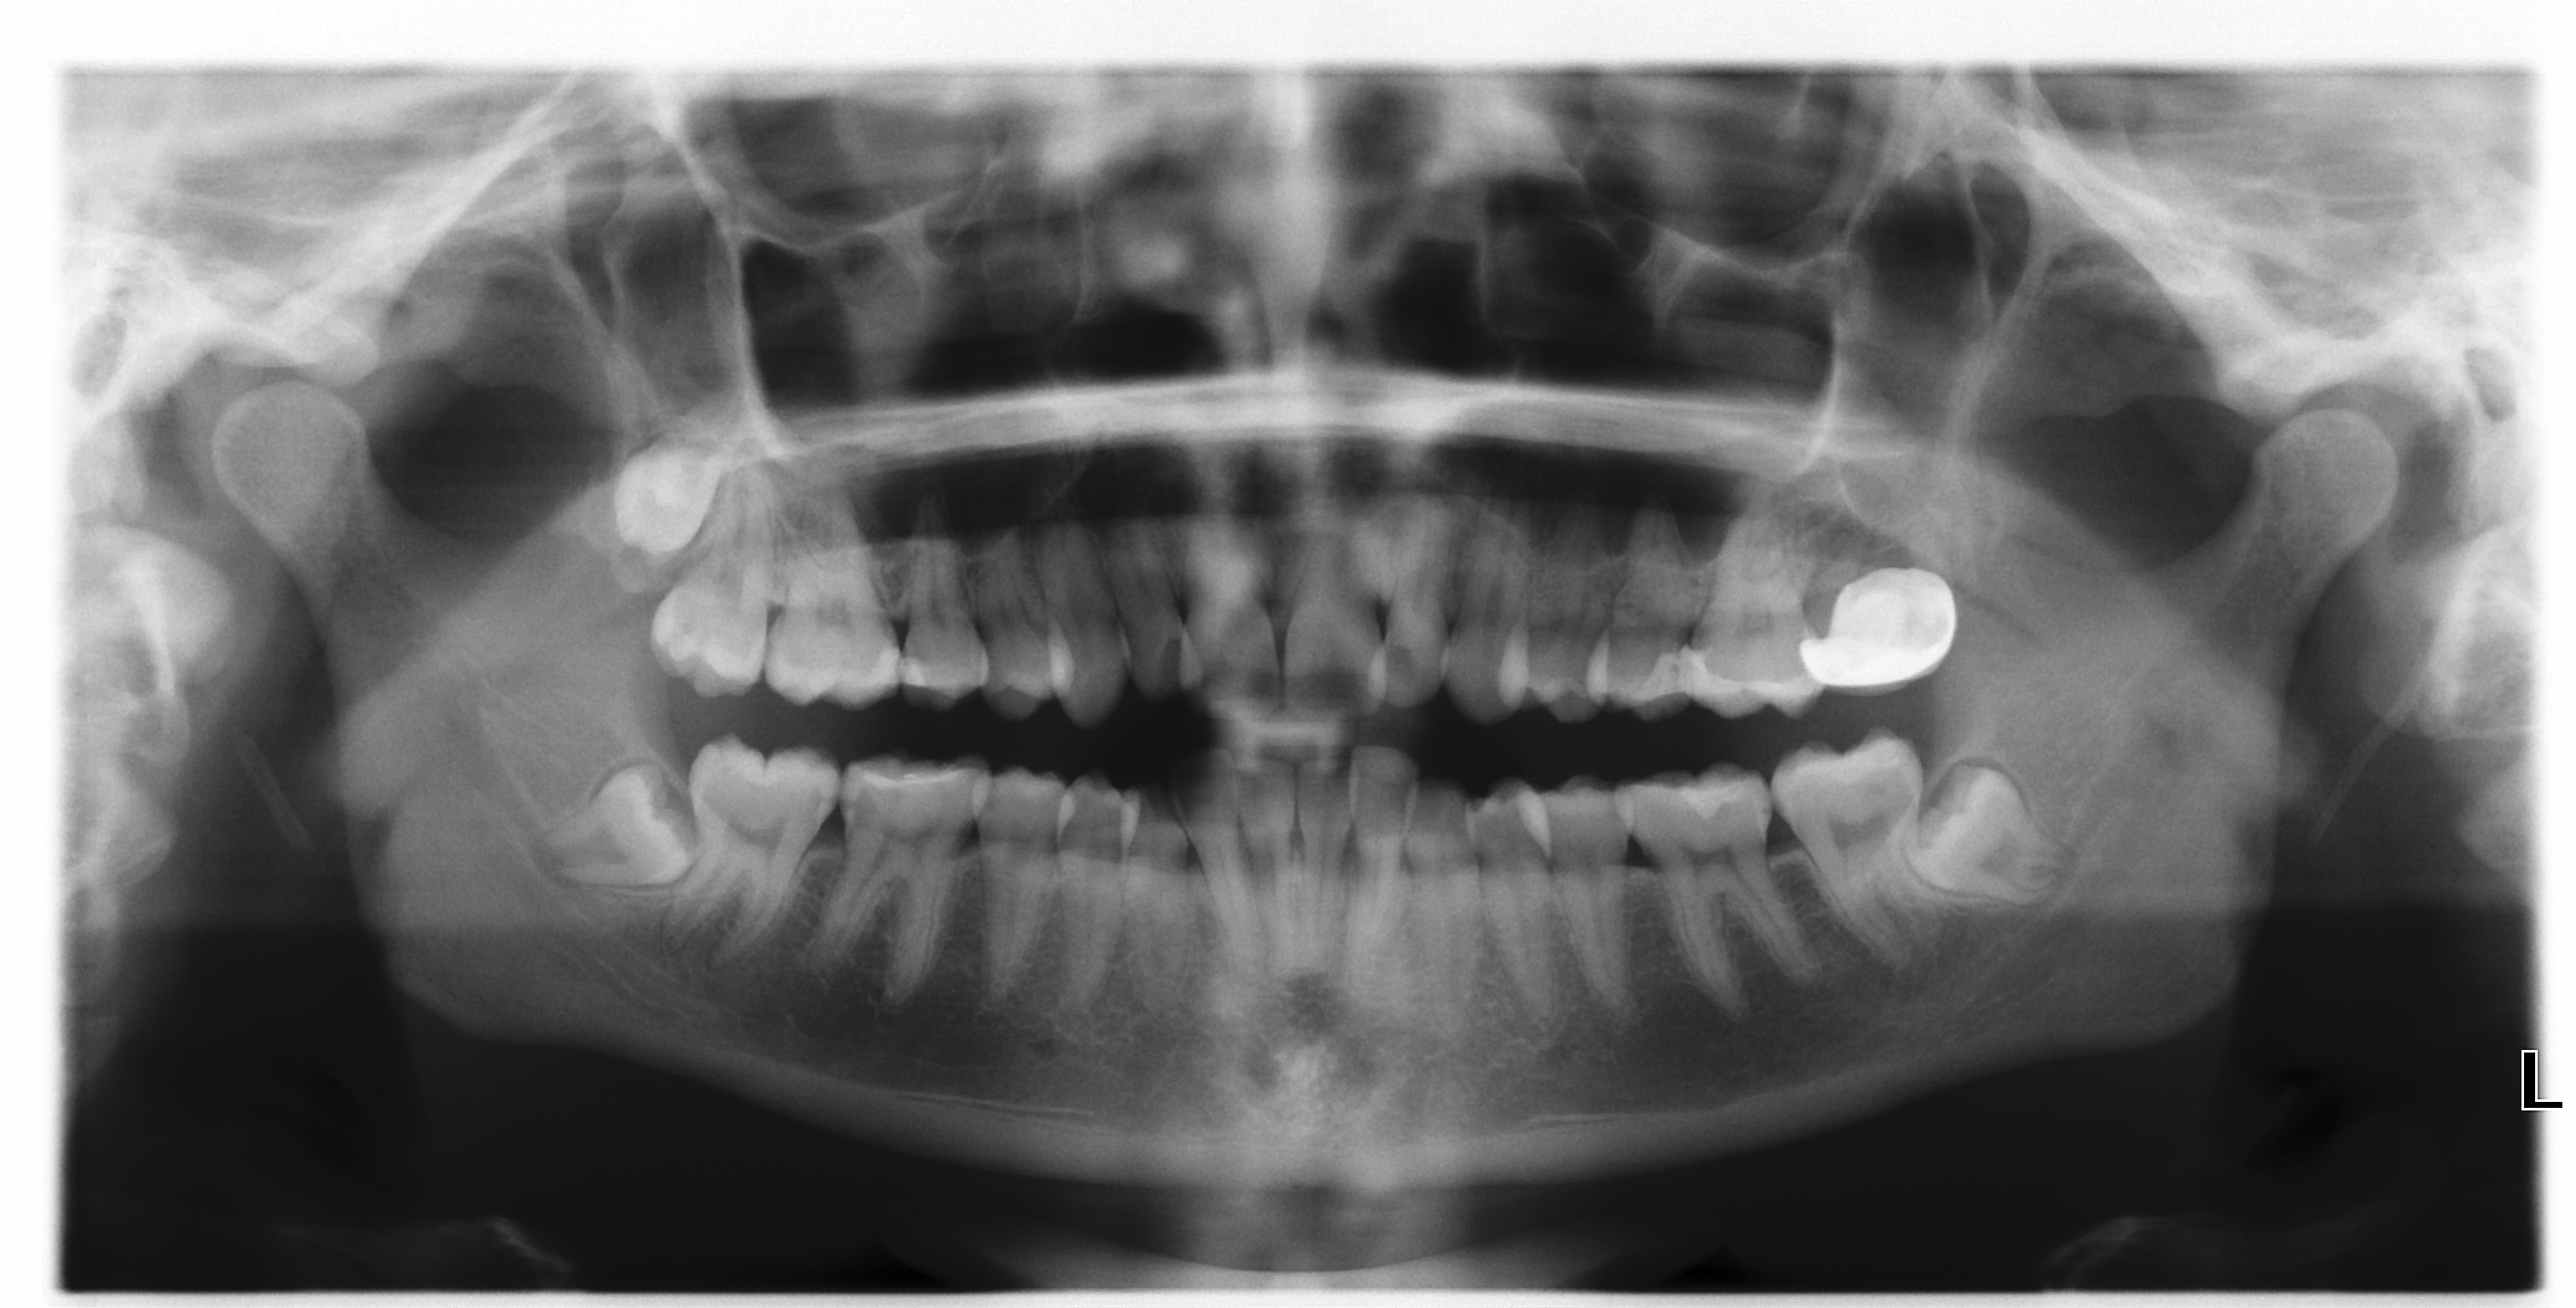

A korszerű, digitális, intraorális (egy-egy fogról felvételt készítő) és panoráma (a teljes fogsorokról felvételt készítő) röntgen-készülékeinkkel készülő képek pár másodperc elteltével máris megjelennek számítógép monitorunkon.

A röntgen-felvételeket azért készítjük, hogy az ön fogain-, vagy azok gyökerén lévő, szabad szemmel nem látható – sőt fájdalommal sem mindig járó, ezért nem érezhető – elváltozásokat is észrevegyük és kezelhessük.